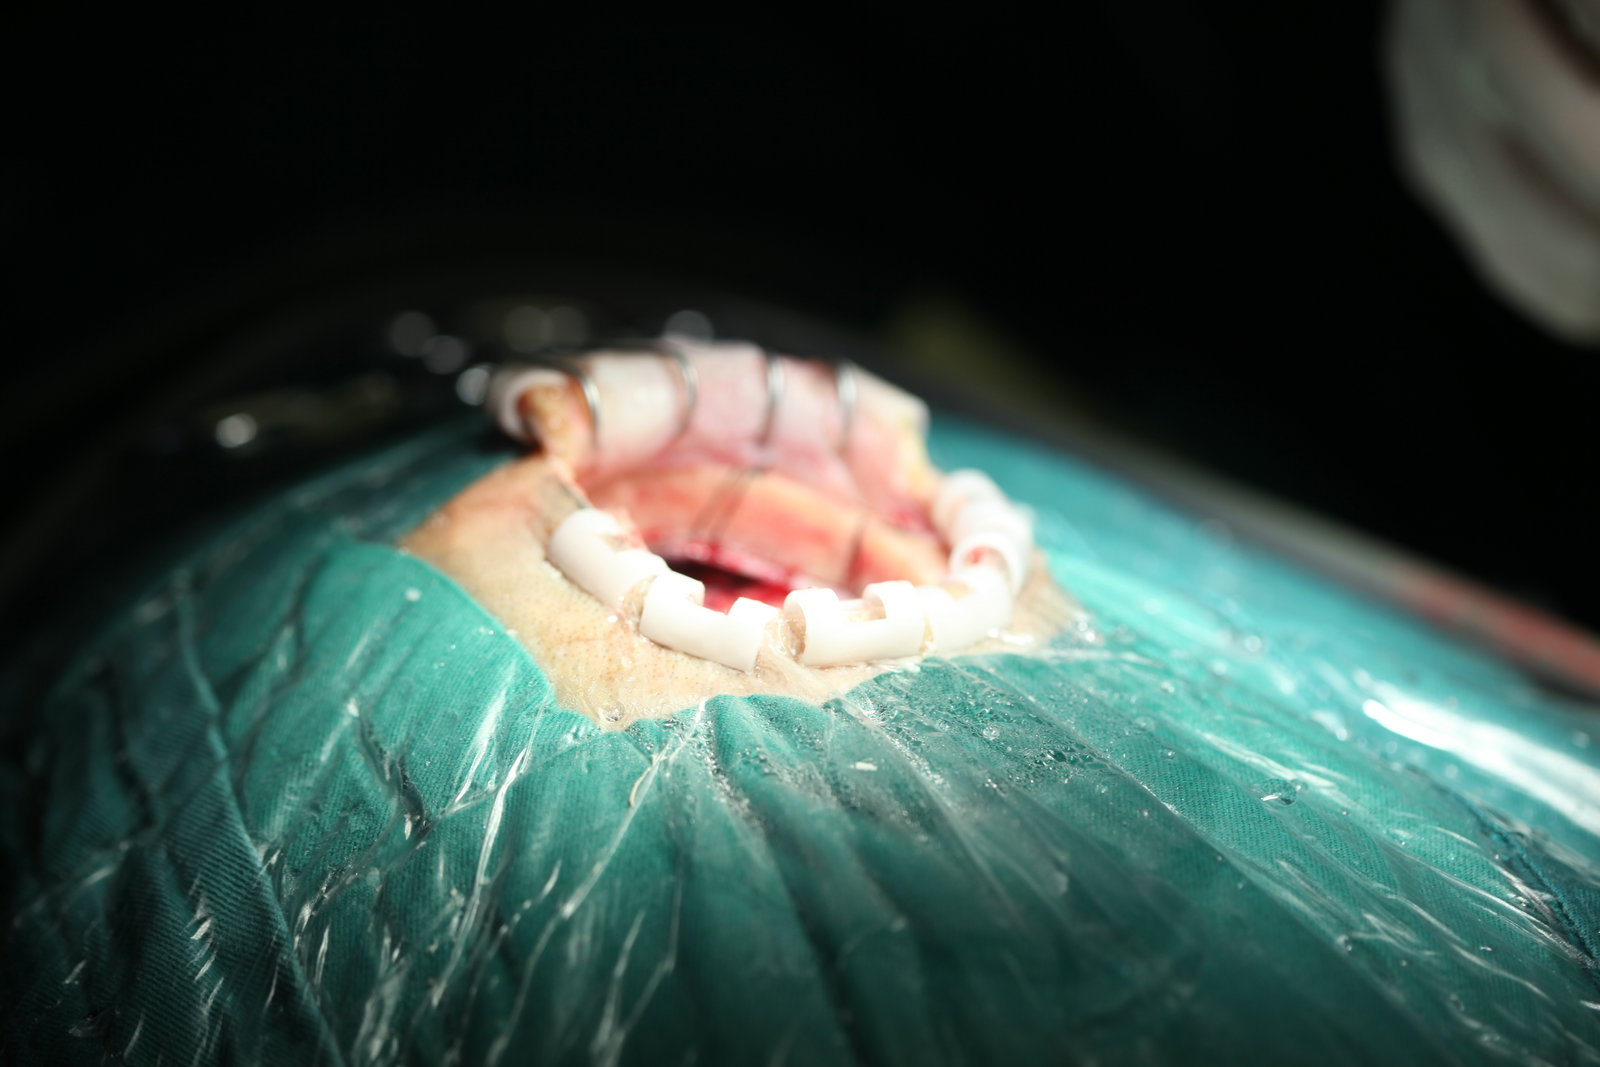

1.以病灶性为中心手术,减少脑组织损伤:显微神经外科手术将经典神经外科“脑叶范围手术”,推向“病灶性手术”水平,尽量减少干扰脑组织,探索出新的手术入路。譬如,翼点入路、经岩骨入路以及额眶颧入路,这些具有代表性显微手术入路的共同特点是,牺牲部分颅底骨结构获得手术空间,经过脑外抵达病灶,尽量减少对脑的牵拉和损伤。20世纪70年代,Yasargil提出利用颅内自然的解剖间隙和经脑外到达病灶部位,处理病变,降低手术创伤,成为了显微神经外科手术的基本概念。随着对脑功能认识的逐步深入,手术中还对各种神经和脑血流进行监测,加大了对脑和神经的功能保护。

2.手术显微镜下全新的手术操作模式:神经外科是从外科发展而来,经典神经外科时期,手术需要2~3名医师完成,手术中强调的是医师之间的相互配合。而显微神经外科手术中,应用众多的显微手术器械,替代了人手的功能,比如自动脑牵开器,代替了助手牵拉脑压板;显微镜的光线代替了带灯脑压板等,手术中的主要关键性操作,基本是由一位医师完成的。另外,为了减少手术损伤,缩小手术野,无法容纳过多的手术器械操作,这就要求手术医师加强训练,特别是术者本人的子、眼配合,左、右手的动作的协调。通常,右利手的医师,固定用左手持吸引器,右乎操作处理病灶。右手最常用的器械是双极电烧镊。在显微手术中,要求手术者的眼睛尽量少的离开目镜,用余光和手的本体觉去寻找和交换手中的器物。手术者还应该学会用右手与器械护士更换器械。手术中常用的双极电烧镊、棉条板置于手术者余光可见到的范围内,手术医师在手术操作中,还需要利用自己肢体的本体觉去完成某些动作,比如手术者固定使用右足踩双极电凝或颅钻的脚闸,左足踏超声吸引器踏板。为尽量少的干扰脑组织,减少频繁的更换器械,还应该充分发挥器械作用,如吸引器可用于做牵开器,双极电凝镊除了可持夹棉条、明胶海绵外,可以用作分离血管、神经的剥离子。手术中尽量少的更换器械,还可以节省手术时间。

2.显微神经外科的器械设备: “欲善其事,必先利其器”。显微神经外科手术之所以能高质量的完成,与精良的显微神经外科的设备和器械分不开 显微神经外科的设备配备不齐全、质量不佳或使用不当,都会影响显微神经外科手术的效果。以手术显微镜为核心的一系列显微手术器械(材),如高速颅钻、可控手术床与头架、自动脑牵开器、超声吸引器、双极电凝、止血纱布等应用,解决了困惑神经外科手术的照明、手术空间狭小和有别于其他外科的止血问题。显微神经解剖学与外科手术技术的巩固和提高相伴。 显微神经外科解剖对于传统的手术技术改进和完善,适应新的条件都十分重要。每年神经外科技术都会有新进展,以适应患者的治疗需求,这些新技术无一不是在深入理解显微神经外科解剖的基础上进行的工作。